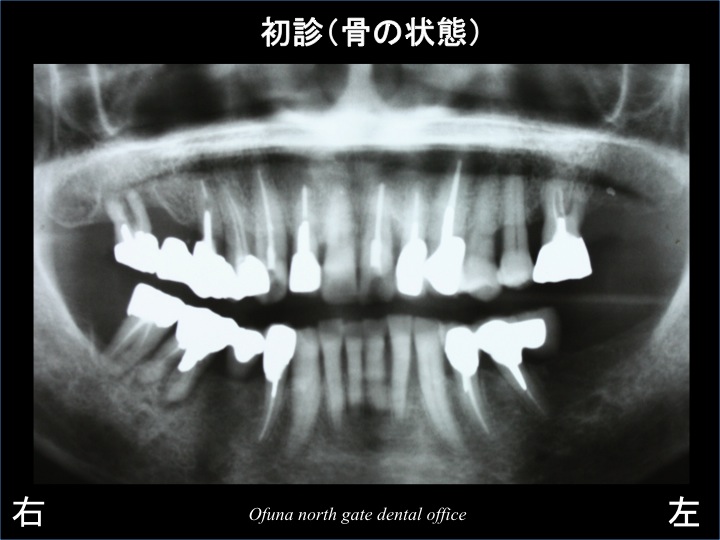

それでは、初診時のレントゲンから見てみましょう。

初診時 上顎前歯部の被せ物が脱離を起こし来院されました。

診査の結果、上顎前歯部が歯根破折 していました。